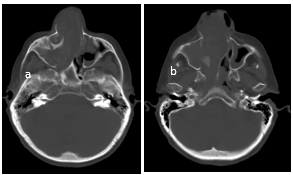

En la ventana ósea se destacan signos de marcada remodelación ósea predominantemente de los senos maxilar derecho y fosa nasal (Figura 4).

Se considera que las estructuras óseas encontradas se deben a restos de celdillas etmoidales y cornetes embebidos en el seno de la masa tumoral. “La localización en zonas como el seno frontal, las celdillas etmoidales supraorbitarias o la región periorbitaria, contraindican la cirugía por vía endoscópica” (Bernardo, Hernández, Calvo, Llorente, & Gómez, 2001); (Aderito, Urdaneta Lafée, Abreu-Durán, & Rodríguez-Hernández, 2017).